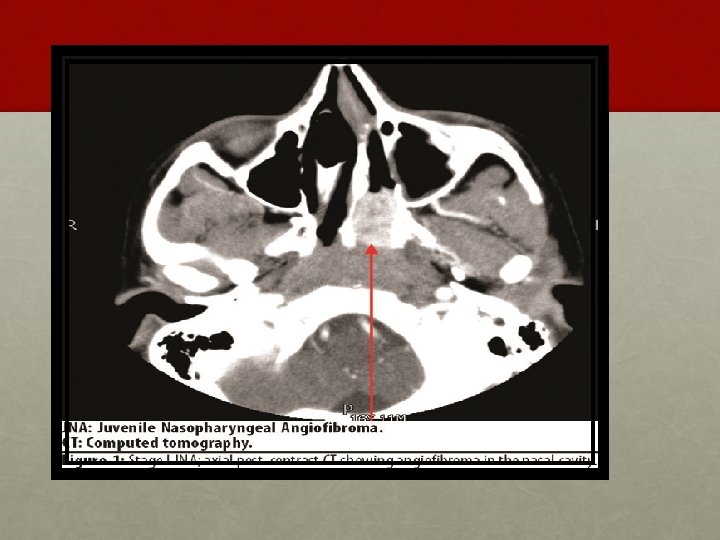

INVESTIGATION: • Contrast enhanced CT scan of nose and PNS • Holman Miller sign/ Antral sign • MRI – soft tissue extent

• Holman miller sign